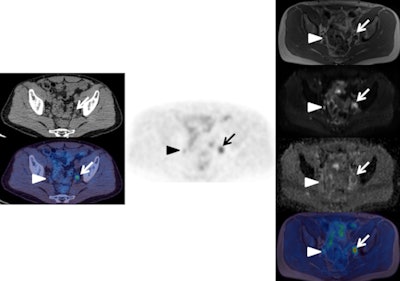

Left: F-18 choline PET/CT (CT top and fused PET/CT bottom). Center: F-18 choline PET. Right: MRI (from top to bottom: T1, b900 diffusion-weighted image [DWI], apparent diffusion coefficient [ADC] map, fused PET/T1 MRI). These images show an enlarged choline-avid left pelvic lymph node in a man with high-risk Gleason 4+5 prostate cancer. This is clearly seen (arrow) on the PET/CT images, as well as on all the MRI sequences (high signal on b900 and restricted diffusion on ADC map). There is a small equivocal focus of uptake on the PET scan in the right side of the pelvis (arrow head), but it is difficult to confirm this is a lymph node on the CT and fused PET/CT images. The MRI sequences confirm a small lymph node with high signal on b900 DWI and restricted diffusion on ADC map (arrowhead). This case shows how the superior tissue contrast and anatomical resolution of MRI sequences allow a better definition of the cause of the right-sided pelvic PET activity and a much more confident diagnosis of right as well as left lymph node involvement. All images courtesy of Dr. Gary Cook."There may well be some new indications that are currently not routine with PET/CT that become adopted by PET/MRI," he explained, adding that these are likely to include novel tracers such as gallium-68 (68Ga) tracer, binding to prostate-specific membrane antigen (PSMA), as well as more conventional ones like F-18 fluorodeoxyglucose (F-18 FDG). "With regards to research, there is a great opportunity to exploit the synergistic potential of having molecular, functional, and anatomical data acquired simultaneously, especially for biological processes that may vary over time and where both PET and MRI signals can contribute, e.g., tumor hypoxia."